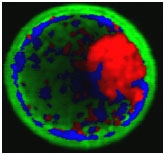

The XploRA INV also offers the option to integrate the unique scanning capabilities of HORIBA’s patented DuoScan for rapid spectroscopic multichannel Raman imaging, as well as the new 3D FCI (Fast Confocal Imaging) module, which allows ultra-fast fluorescence imaging for visualisation and verification.

White light image (left), fluorescence FCI image (center) and hyperspectral fluorescence image (right) images of a bovine embryo after staining with Nile Red, acquired on the XploRA INV. The hyperspectral image illustrates the stain in different polarity states. Data courtesy of Prof. Igor Chourpa, Université de Tours, France.